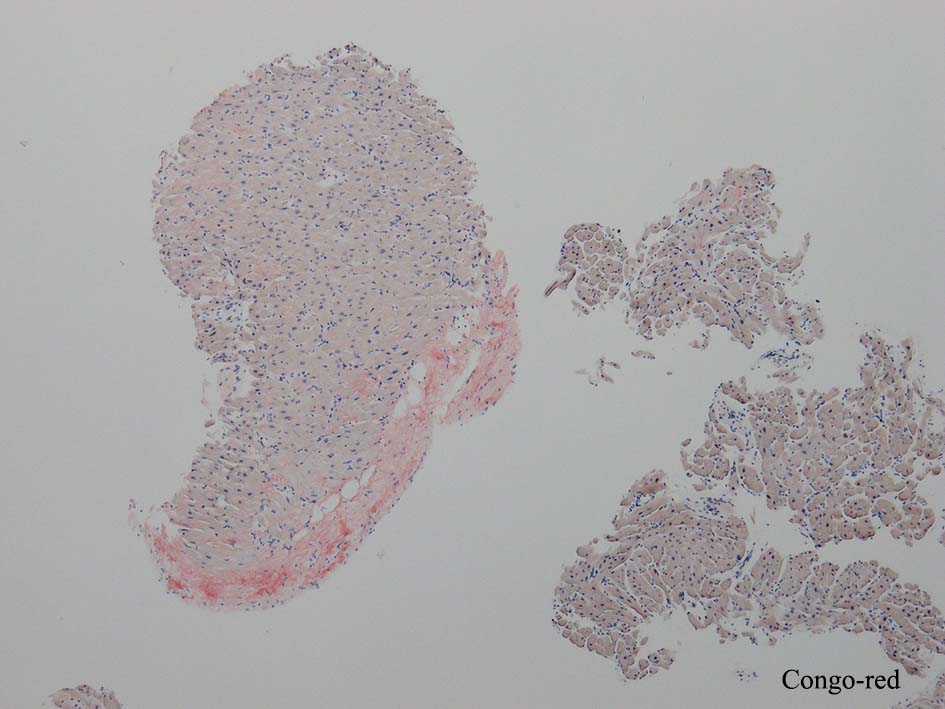

HE所見では, 明瞭な沈着物はわかりにくい. 血管壁が確認できる血管も少ない. congo-red染色で沈着が考えられる所見があり, 簡易偏光で(みずらいけれど)apple-greenの偏光があるように見える.(サムネイルのクリックで大きな画像が見られます)